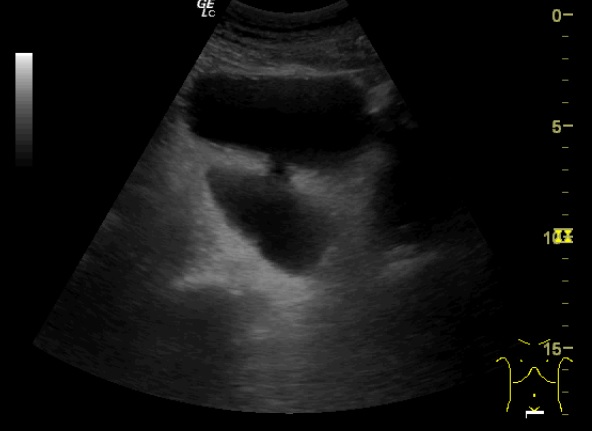

Glándula prostática de 4,28 x 5,81 x 4,57 cm (Figura 1). Volumen prostático: 59,45 ml. Pared de vejiga no engrosada. Se objetiva divertículo vesical (Figura 2) único localizado en pared postero lateral. No se observan lesiones intravesicales ni tampoco en la luz del divertículo (Figura 3). Volumen posmiccional 240 cc.